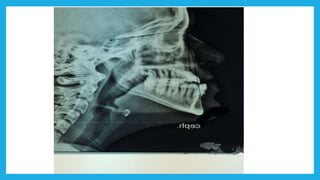

 Radiographic assessment of the patient